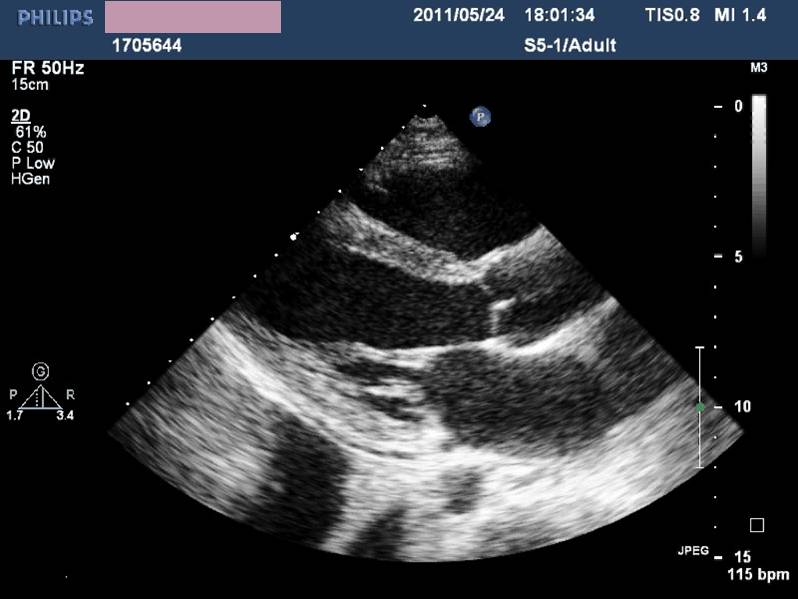

——床旁超声心动:节段性室壁运动异常,左房增大,轻度二尖瓣关闭不全,左室收缩功能减低,LVEF 45%,少量心包积液

现病史-超声心动

急性左心收缩功能不全

心功能不全IV级